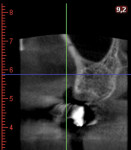

The treatment plan called for harvesting a cortico-cancellous autogenous bone block with its connective tissue and epithelium from the tuberosity. Therefore, a segmental cone-beam computed tomography (CBCT) scan was taken to assess the dimensions of the tuberosity and the position of the sinus floor and to avoid oroantral communication. Soft-tissue thickness was evaluated with a periodontal probe, and a square outline was drawn on the right tuberosity with a 15C blade, reaching the bone. Incisions were made 2 mm away from the lateral margins of the tuberosity and 1 mm away from the distal surface of the last molar. Incisions were designed perpendicularly to the coronal aspect of the tuberosity and slightly angulated from the outer part to the inner side of the bone. The graft was then harvested with a bone chisel and mallet (Figure 7).

After 4 months, the peri-implant soft tissues appeared healthy, and the probing depths ranged from 3 mm to 4 mm with no bleeding on probing. A digital impression was made, and the final implant-supported zirconia crown was delivered 2 weeks later. The bone around the implant head was radiographically stable at the 2-year follow-up, with only a slight sign of remodeling around the abutment connection (Figure 11 and Figure 12). The CBCT showed a buccal bone plate with 2 mm of thickness on the facial aspect of the implant, and no increase in gingival recession was noted (Figure 13).